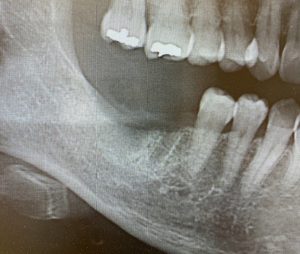

当院での骨造成の症例です

抜歯後三ヶ月のレントゲン写真